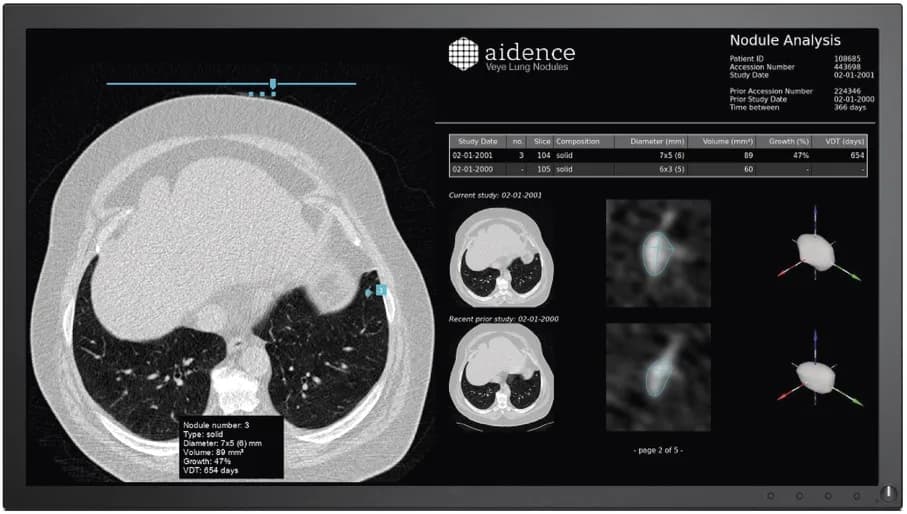

Amsterdam-based Aidence combines data science and healthcare by developing artificial intelligence solutions for the field of oncology. Their first tool, Veye Lung Nodules, helps radiologists identify and characterise pulmonary nodules – small growths on the lung – and track their progression. These nodules, particularly if they change size or shape over time, could be cancerous and catching these markers early can help increase survival rates. A recent NELSON study showed that CT screening for nodule volume management reduces lung cancer mortality by 26%, and more research is underway to further explore the impact of CT screening in improving patient outcomes.

Eventually the algorithm was able to independently learn and improve on its ability to identify the characteristics of nodules, noting their size, volume and opacity. It also automatically checks a patient’s previous scans to determine if the growths have changed size or shape over time. This simplifies reporting and helps radiologists supply all the most relevant data to referring physicians.